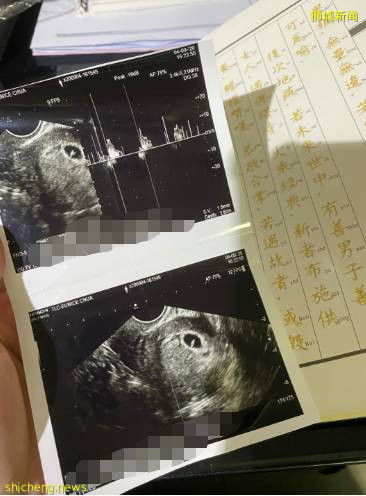

懷孕3個月,我做了乳癌手術

我是一個癌症患者,在發現剛剛懷孕的時候,我被檢查出乳腺癌,醫生都建議我一邊做腫瘤切除手術一邊做流産手術。

最後,我還是選擇留下孩子!我相信我和孩子都會挺過去,寶寶在我肚子裏3個月的時候,我做了腫瘤切除手術。在手術室7個小時,還進了ICU,所幸最終母子平安。

乳癌術後2年,我又懷孕了…

最終,我再次決定留下孩子!